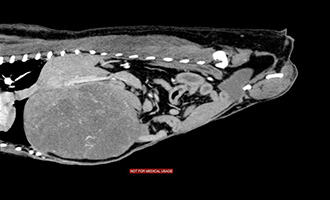

術前CT画像 |